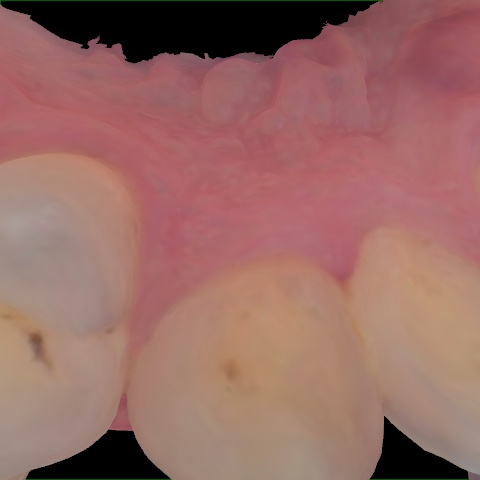

Image 72 / 2000

NHD39969

Annotated as "Good"

Original Image Rendering Image